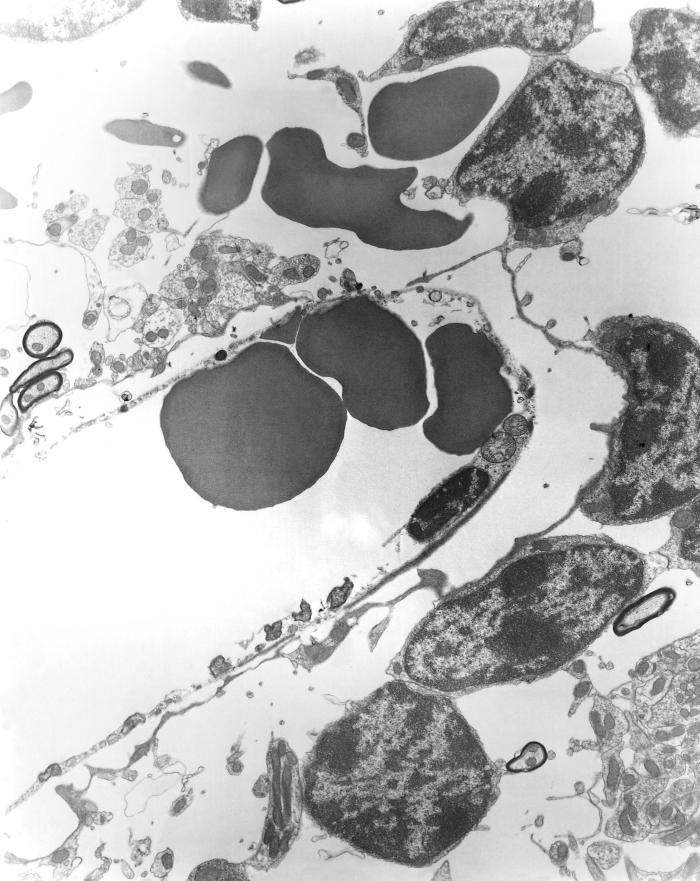

This 1976 transmission electron microscopic (TEM) image depicted a brain capillary of a mouse that had been experimentally infected with Orientia tsutsugamushi rickettsial micro-organisms. Revealed, was the presence of pericapillary hemorrhage and edema. Several of the O. tsutsugamushi organisms were visible within the cytoplasm of a degenerating capillary endothelial cell. Formerly known as Rickettsia tsutsugamushi, O. tsutsugamushi is the pathogen responsible for causing the febrile disease known as scrub typhus. The disease is transmitted to humans through the bite of larval trombiculid mites, i.e., chiggers, that had fed on infected rodents.